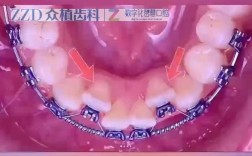

🦷 2. 根管治疗(杜牙根)

- 适用情况: 龋齿已导致牙髓感染或坏死(表现为剧烈自发性疼痛、夜间痛、冷热刺激痛持续、热痛冷缓解、牙髓活力测试无反应),或已发展为根尖周炎(表现为牙根尖处有脓包、牙龈反复肿胀流脓、牙齿浮起感、叩痛明显)。